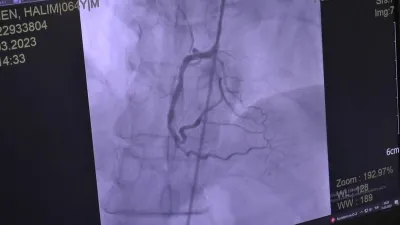

Check-up Yaptırdı Hayatı Kurtuldu -